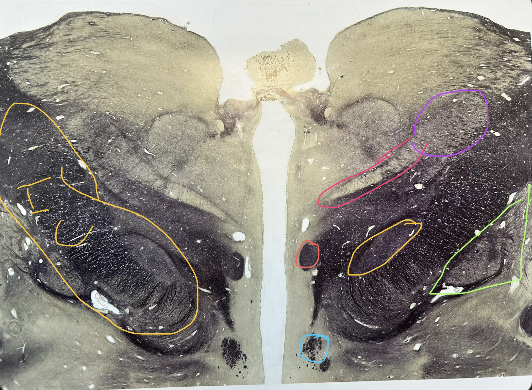

whats in yellow

subthalamic nucleus

whats in green

globus pallidus, internal and external

whats in salmon

mammilothalamic tract

whats in pink

ventral posteromedial nucleus of thalamus

whats in purple

ventral posterolateral nucleus of thalamus

whats in blue

column of fornix